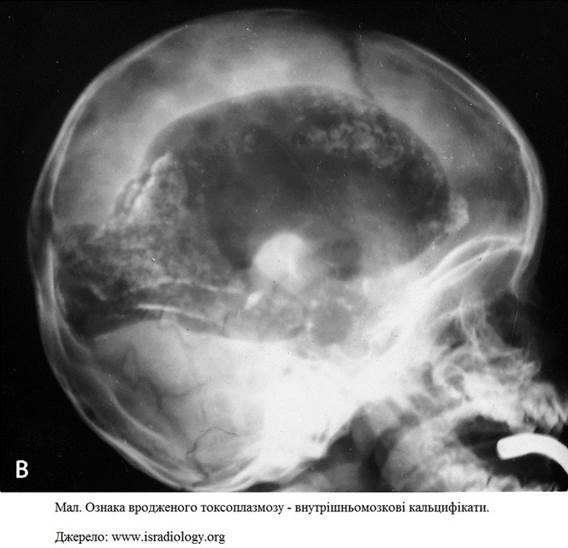

внутрішньомозкові кальцифікати.

Тяжкі форми вродженого токсоплазмозу

характеризуються тріадою

симптомів:

- гідроцефалія,

- внутрішньомозкові кальцифікати,

- хоріоретиніт.